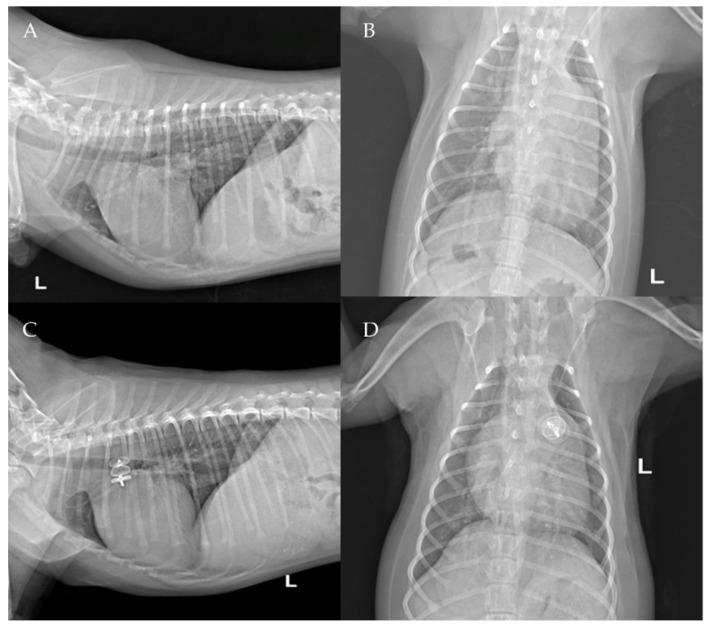

Although vascular plugs for the closure of patent ductus arteriosus (PDA) have been validated in dogs, studies are lacking on its use as a first-choice device with a transjugular approach. The present case series describes the transvenous right jugular embolization of PDA using an Amplatzer Vascular Plug II in seven dogs of different ages, breeds, and body weights. Complete closure of the PDA was demonstrated in all cases. All dogs showed significant hemodynamic reduction of pulmonary overcirculation and left heart size after the procedure and at following echocardiographic check-ups. Transjugular PDA occlusion using an Amplatzer Vascular Plug II can thus be considered as a safe alternative to the arterial or venous femoral approach using an Amplatzer canine ductal occluder (ACDO), particularly in puppies with small femoral vessels.

尽管用于闭合动脉导管未闭(PDA)的血管封堵器已在犬类中得到验证,但缺乏关于将其作为经颈静脉途径的首选装置的研究。本病例系列描述了使用Amplatzer血管封堵器II对7只不同年龄、品种和体重的犬经静脉右颈静脉进行PDA栓塞。所有病例均显示PDA完全闭合。所有犬在术后及随后的超声心动图检查中均显示肺循环过度和左心大小显著降低。因此,使用Amplatzer血管封堵器II经颈静脉封堵PDA可被视为使用Amplatzer犬用导管封堵器(ACDO)经动脉或股静脉途径的安全替代方法,特别是对于股血管较小的幼犬。